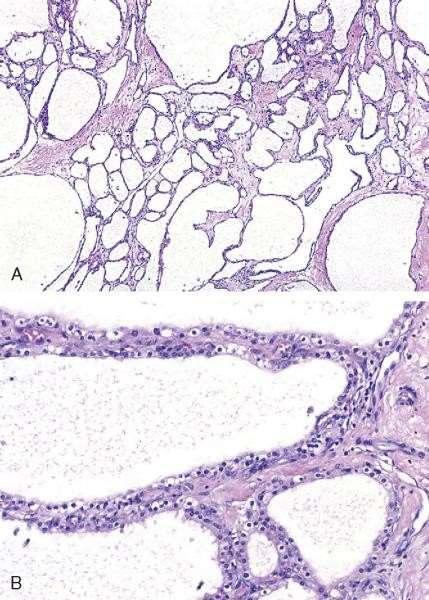

Serous cystadenoma

• Most common type of cystic

• Body, tail

• Predominantly in females

neoplasm

Mucinous cystadenoma

• Macrocystic

• Almost exclusively in females

• Tail

• Pathology: mucinous glands and ovarianlike stroma